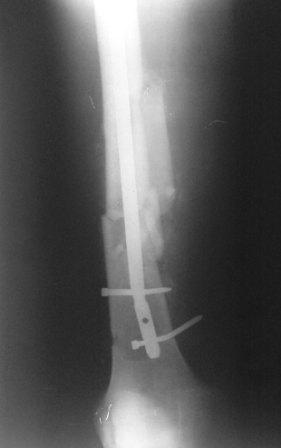

Пациент с политравмой. Выполнен помимо всего остеосинтез бедра стержнем. Поступил через месяц после операции с переломом фиксатора.У нас возникли разногласия по дальнейшей такике.Помогите пожалуйста советом! Пациент, 30 лет, после мотоциклетной аварии получил следующие повреждения: перелом бедра, перелом вертлужной впадины на противоположной стороне, перелом обоих предплечий, ЧМТ.Выполнен остеосинтез таза пластиной и остеосинтез бедра стержнем ChM. Во время операции стержень оптимальной длины оказался слишком "толстым" (420/11 мм) и пришлось выбрать более короткий гвоздь (400/10 мм). Через месяц возникла следующая картина: изгиб винтов и стержня, появилось смещение, имеется тугая подвижность в месте перелома.Предложено несколько выходов:- поменять фиксацию на более длинный гвоздь,- использовать ретроградную версию бедренного гвоздя,- поменять на накостный фиксатор (длинную LCP DF).В данном случае приобретать импланты придется за счет средств пациента, поэтому хотелось бы все тщательно взвесить.Уважаемые коллеги, помогите пожалуйста советом, как бы вы поступили в такой ситуации.

Большое спасибо за ответы. Прошу прощения, что сразу не показал боковую проекцию (прилагаю сейчас). Может быть с таким торцевым упором не производить динамичсекую фиксацию, а провести динамизацию позже.